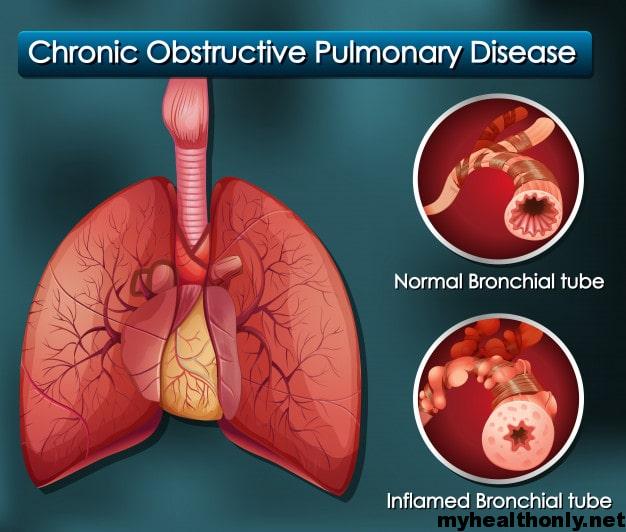

COPD (Chronic Obstructive Pulmonary Disease) My Health Only

DPOC (doença pulmonar obstrutiva crônica) é um conjunto de doenças respiratórias, como bronquite crônica e enfisema pulmonar, que bloqueiam as vias aéreas e dificultam a respiração. A principal causa da DPOC é o tabagismo, pois a fumaça e outras substâncias presentes no cigarro prejudicam o tecido das vias respiratórias, levando ao.

A doença pulmonar obstrutiva crônica (DPOC) caracteriza-se pela limitação crônica ao fluxo aéreo, não totalmente reversível, associada a uma resposta inflamatória anormal à inalação de partículas ou gases nocivos.

Poluição do ar intra e extradomiciliar. Na DPOC, ocorre inflamação crônica das vias aéreas centrais e periféricas, parênquima e vasos pulmonares em resposta à inalação de partículas e gases nocivos, com acúmulo principalmente de macrófagos, neutrófilos e linfócitos T (sobretudo CD8).